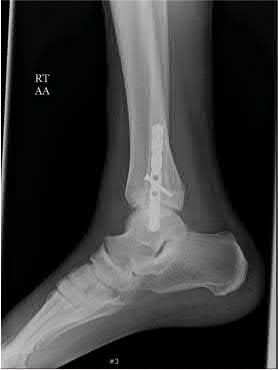

A 64-year-old woman is thrown off a horse, sustaining the injury shown in Figures A and B. She undergoes surgical fixation as seen in Figures C through E. What is the most commonly reported complication of this procedure?

The patient in the scenario has a 2-part proximal humerus fracture treated with a locking plate as seen in Figures A-E. The most common complication with the use of this implant is screw penetration. The terms screw cut out and penetration are often used interchangeably in the literature with cut out appearing more frequently in reports regarding intertrochanteric fractures.

Owsley et al retrospectively reviewed 53 proximal humerus fractures treated with locking plates and the same post-operative protocol. The most common complication was screw cut out or penetration, followed by varus displacement. They concluded that 3 and 4-part fractures in patients over 60 years have a higher incidence of failure.

Agudelo et al retrospectively reviewed 153 patients at a level-one trauma center treated with proximal humerus locking plates, investigating modes of failure for the implant. They determined that varus malreduction (head-shaft angle